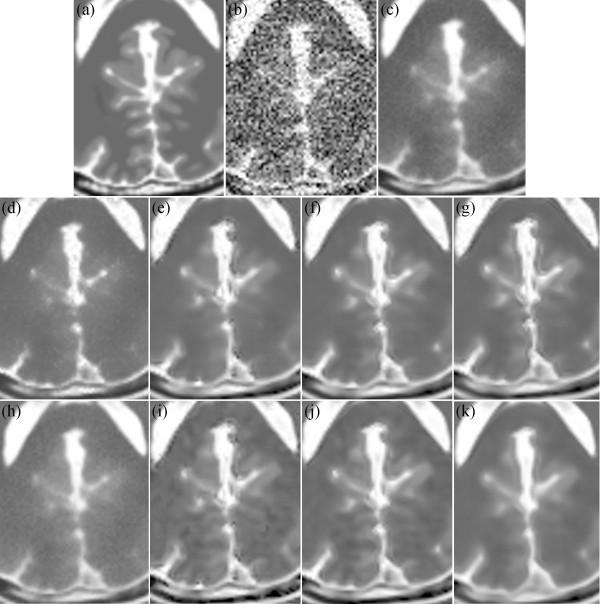

Considering the characteristics of both Rician noise and the NLM filter, this study proposes a frame for a pre-smoothing NLM (PSNLM) filter combined with image transformation. In the PSNLM frame, noisy MRI is first transformed into an image in which noise can be treated as additive noise. Second, the transformed MRI is pre-smoothed via a traditional denoising method. Third, the NLM filter is applied to the transformed MRI, with weights that are computed from the pre-smoothed image. Finally, inverse transformation is performed on the denoised MRI to obtain the denoising results.

To test the performance of the proposed method, both simulated and real patient data are used, and various pre-smoothing (Gaussian, median, and anisotropic filters) and image transformation [squared magnitude of the MRI, and forward and inverse variance-stabilizing trans-formations (VST)] methods are used to reduce noise. The performance of the proposed method is evaluated through visual inspection and quantitative comparison of the peak signal-to-noise ratio of the simulated data. The real data include Alzheimer's disease patients and normal controls. For the real patient data, the performance of the proposed method is evaluated by detecting atrophy regions in the hippocampus and the parahippocampal gyrus.

The comparison of the experimental results demonstrates that using a Gaussian pre-smoothing filter and VST produce the best results for the peak signal-to-noise ratio (PSNR) and atrophy detection.